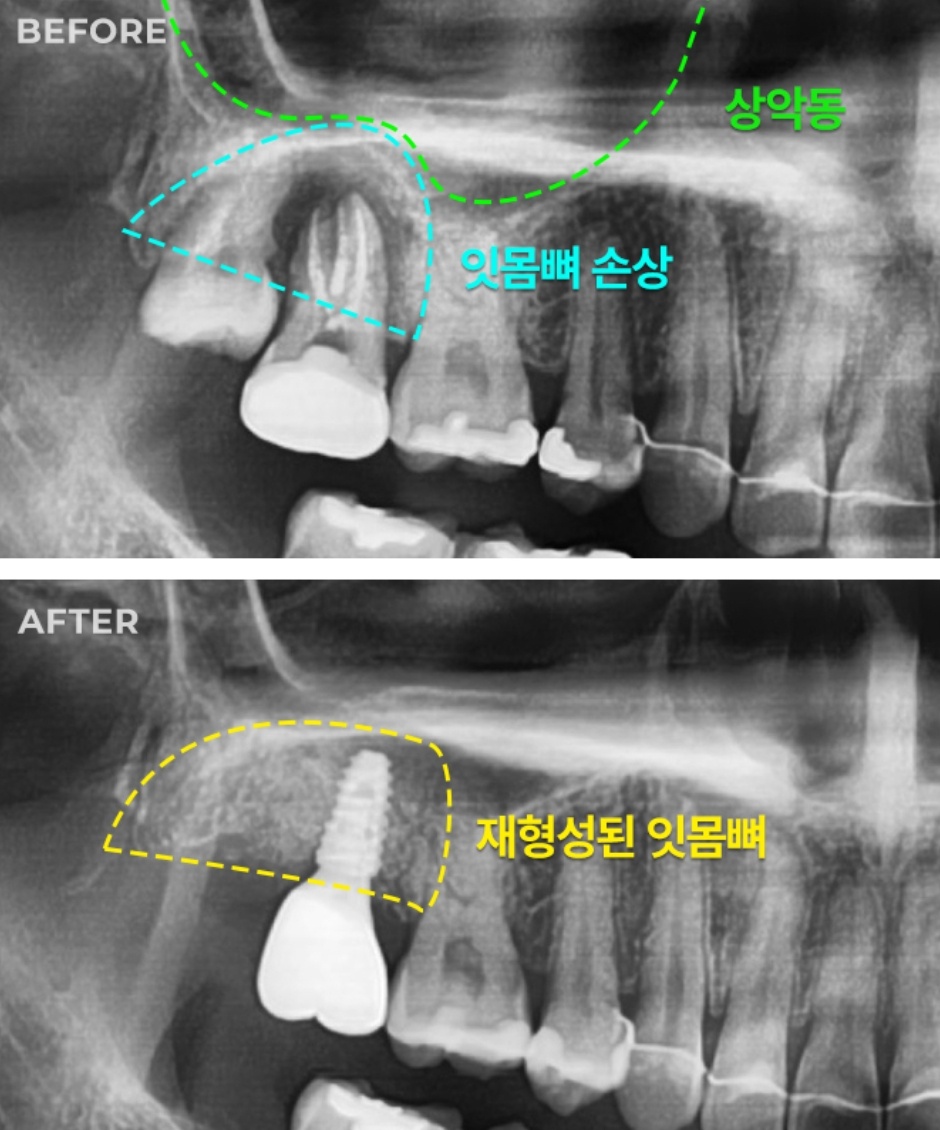

미사랑치과의원은 26년 넘는 임상 경험을 가진 구강악안면외과 전문의 김규영 원장님이 이끄는 곳이라네. 특히 임플란트 시술에 대한 자부심이 대단하신데, 뼈가 부족해서 임플란트가 어렵다는 진단을 받은 환자나, 고난도 케이스로 대학병원을 권유받은 환자들도 3D CT 정밀 진단을 통해 다시 한번 상담받아보시길 추천한다네. 26년 임상 경력의 김규영 박사님은 최상의 치료 결과는 물론, 편안하고 안전한 진료를 제공하기 위해 항상 노력하고 있다고 하니 믿음이 가지 않나?